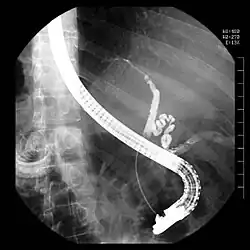

Therapeutische ERCP zur Behebung einer Verengung des Gallengangs infolge einer PSC. Der geschlängelte Gallenblasengang ist gut erkennbar. Blickrichtung ist auf den Rücken des Patienten.

Therapeutisch bedeutsam ist die Möglichkeit, bei Verengungen durch Tumoren oder Entzündungen durch Einbringen von Stent genannten Kunststoff- oder Metallröhrchen den Gallen- und Bauchspeichelfluss wieder zu ermöglichen. Weiterhin ist eine gezielte Entnahme von Proben mit Zangeninstrumenten oder Bürsteninstrumenten möglich, um den Verdacht auf Tumor oder Entzündung mit einer feingeweblichen (histologischen) Untersuchung zu bestätigen.[2] Der Gallengang kann über ein Cholangioskop, das durch den Arbeitskanal des Endoskops vorgeschoben wird, auch direkt eingesehen werden (Mother-Baby-Technik). Weiterhin kann man mit einer ebenfalls durch den Arbeitskanal vorgeschobenen Sonde den Gallengang sonographisch untersuchen, was als intraduktaler Ultraschall (IDUS) bezeichnet wird.